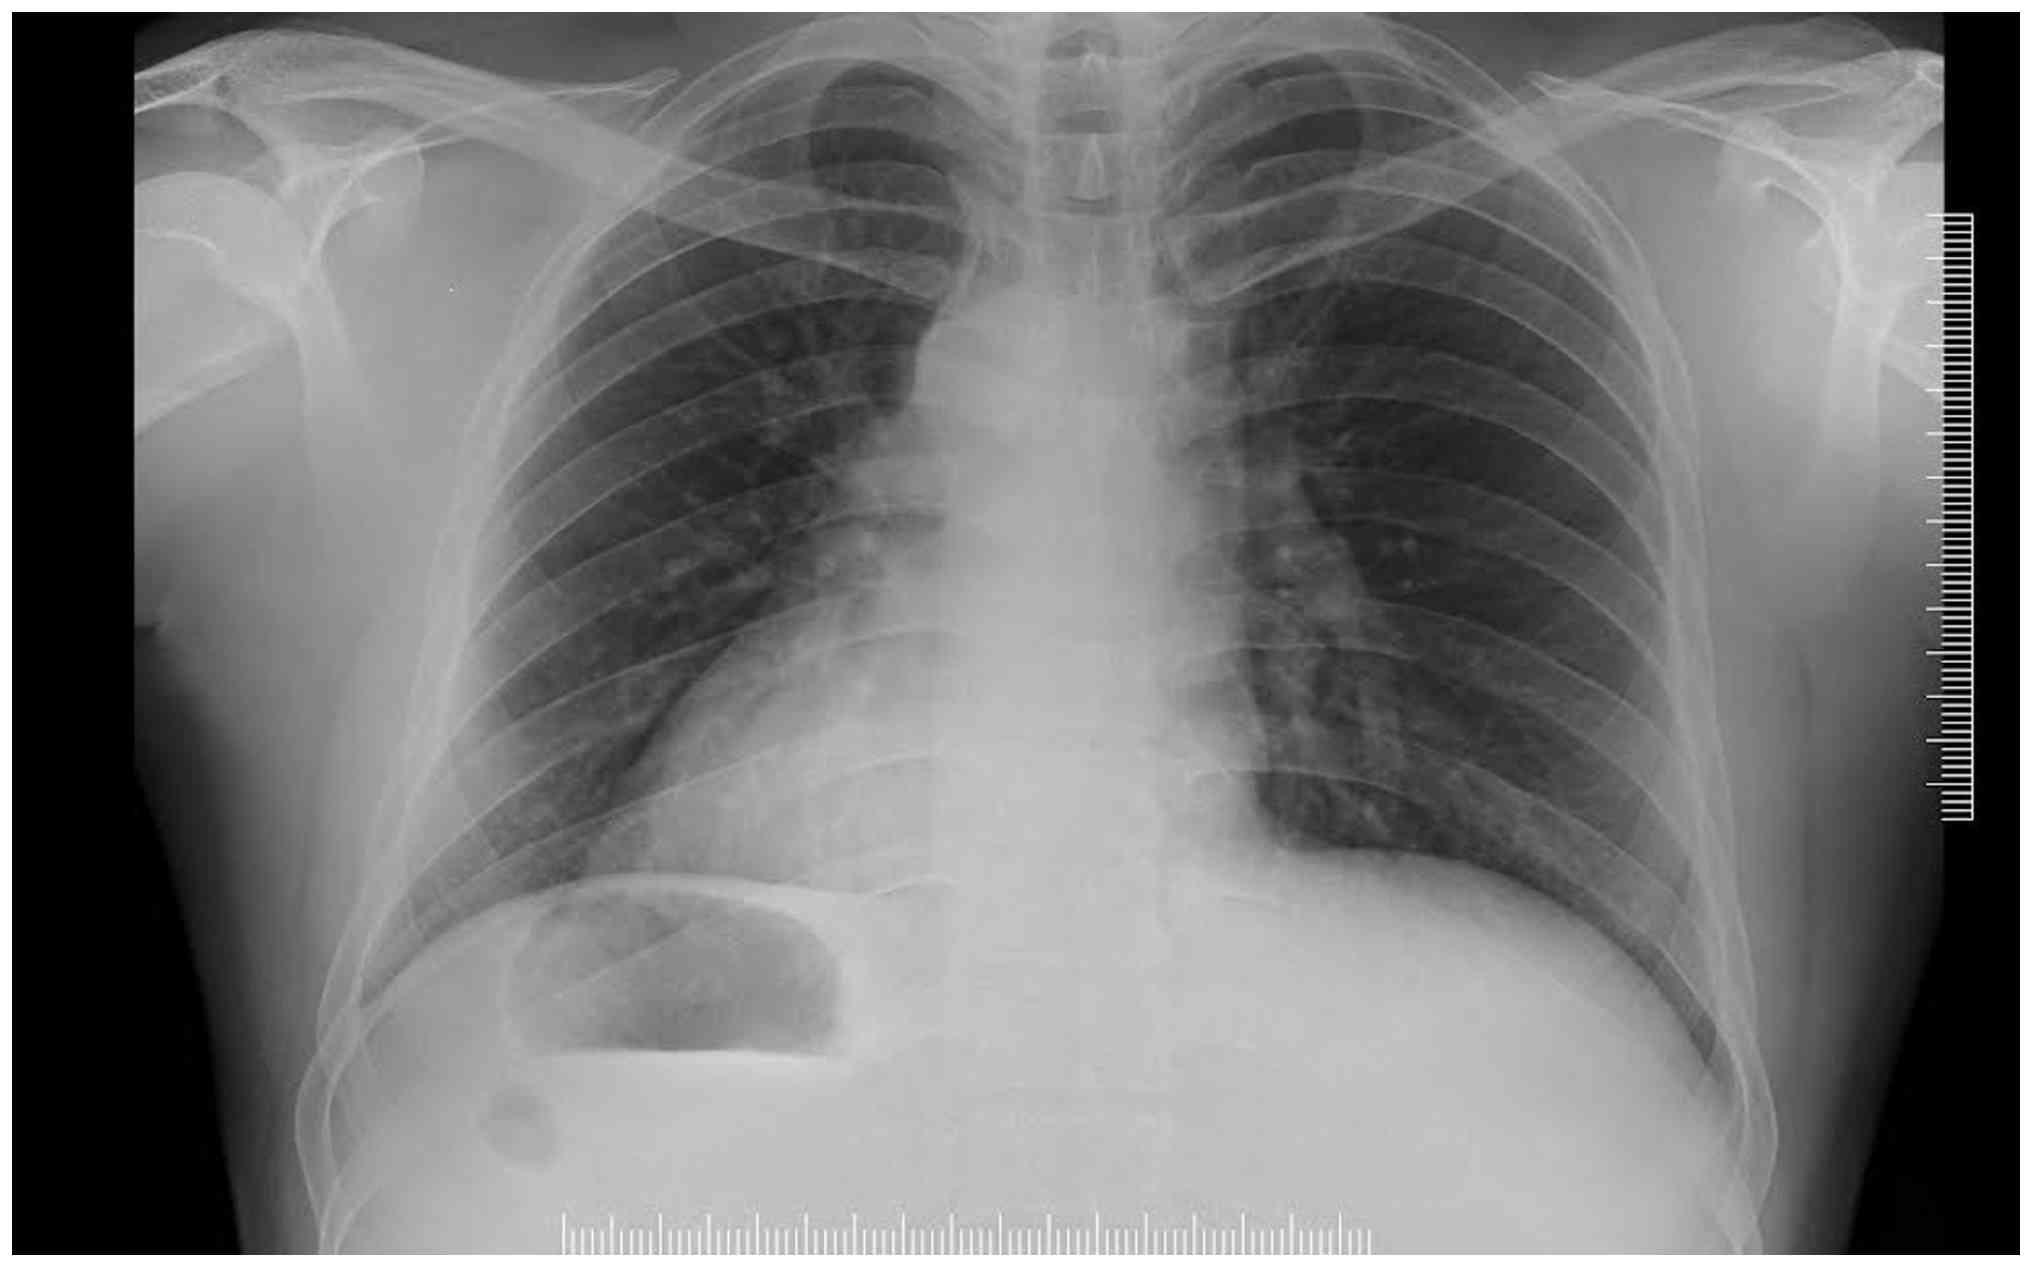

An electrocardiogram revealed sinus rhythm with right axis deviation, a negative QRS complex in Lead 1, and inverted P and T waves in Lead 1, with a progressively decreasing R-wave amplitude from V1 to V6. A chest X-ray demonstrated a right-sided cardiac shadow consistent with dextrocardia (Fig. 1). An electrocardiogram revealed sinus rhythm with right axis deviation, a negative QRS complex in Lead 1, and inverted P and T waves in Lead 1, with a progressively decreasing R-wave amplitude from V1 to V6 (Fig. 2). Ultrasonography showed the spleen on the right (Fig. 3) (splenomegaly 14.5 cm), with normal kidneys, consistent with situs inversus totalis.

Chest X-ray demonstrating a

right-sided cardiac shadow consistent with dextrocardia.

Figure 1

Chest X-ray demonstrating a right-sided cardiac shadow consistent with dextrocardia.